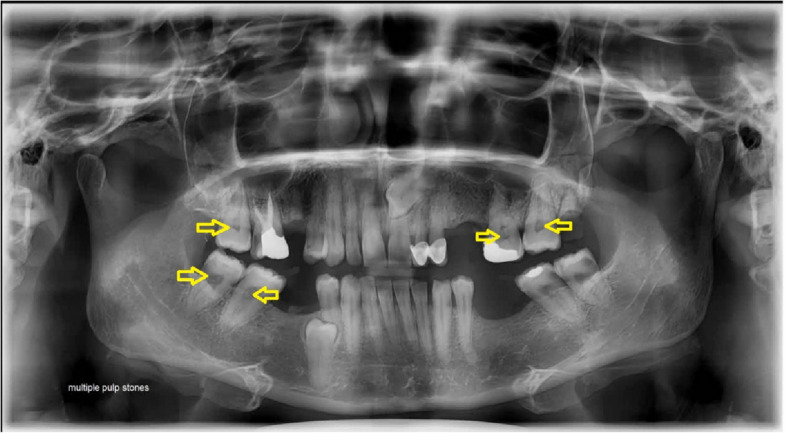

Background: Carotid artery calcifications and pulpal stones are radiopaque findings that may be found accidentally in panoramic views. The risk of affliction with atherosclerotic events in diabetic patients with dystrophic calcification is questionable. This study aimed to investigate the relative frequency of carotid calcifications and pulp stones in panoramic radiographs of diabetic patients.

Results: In this study, panoramic radiographs of 107 diabetic patients (67 women and 40 men) and 300 healthy individuals (196 women and 104 men) were evaluated. The age range was 25 to 64 years, with a mean age of 49.7. The frequency of carotid artery calcification was 42 (14%) in healthy individuals and 44 (41.1%) in diabetic patients. Furthermore, the relative frequency of unilateral and bilateral carotid artery calcification in diabetic patients was significantly higher than in healthy subjects (P < 0.05). The Relative Risk (RR) of pulp stones in the diabetic patient group compared to healthy individuals was 1.8. With a 95% confidence interval, the relative risk ranged from 1.3 to 2.48, which was statistically significant (P < 0.05).

Conclusions: Based on the findings, the frequency of carotid artery calcification and pulp stones was higher in diabetic patients. Panoramic radiographic screening in diabetic patients is useful for early detection of carotid artery calcification and timely referral of patients to endocrinologists to prevent adverse sequelae.